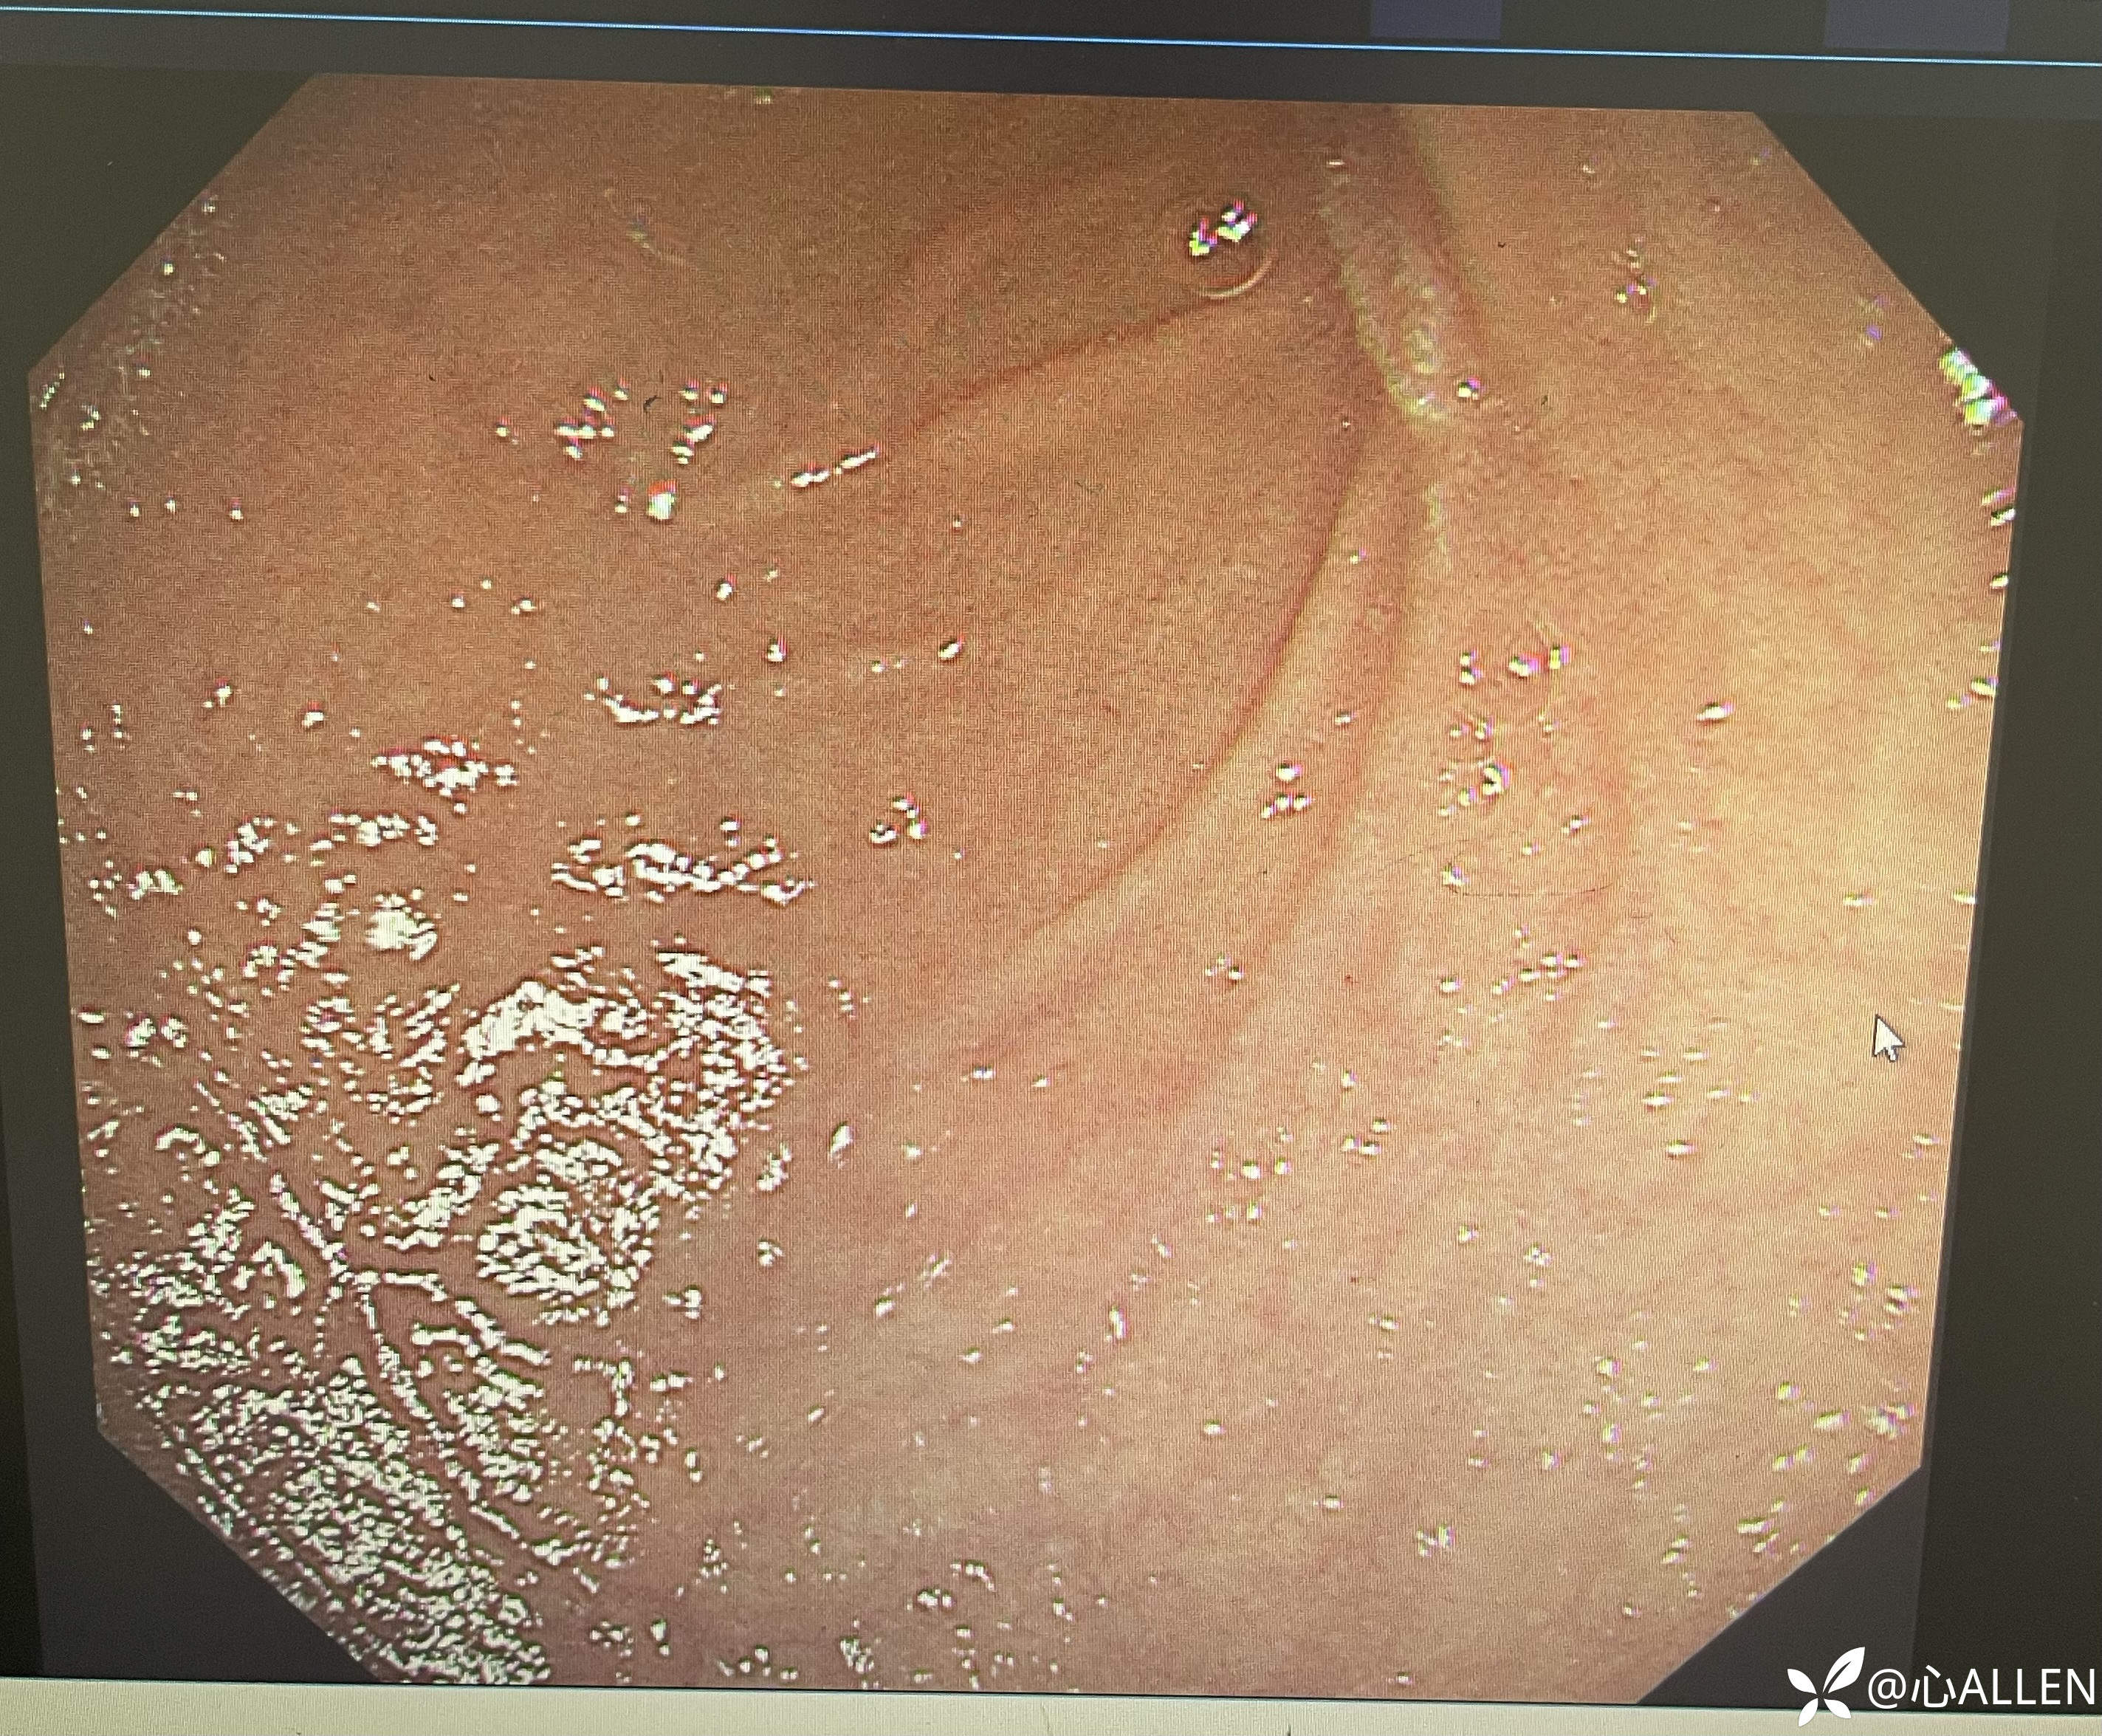

靠近观察球降交界见主乳头

正常右旋up进镜十二指肠降部,发现内镜在球腔倒镜,幽门下方有肠腔

回正镜身观察发现主乳头